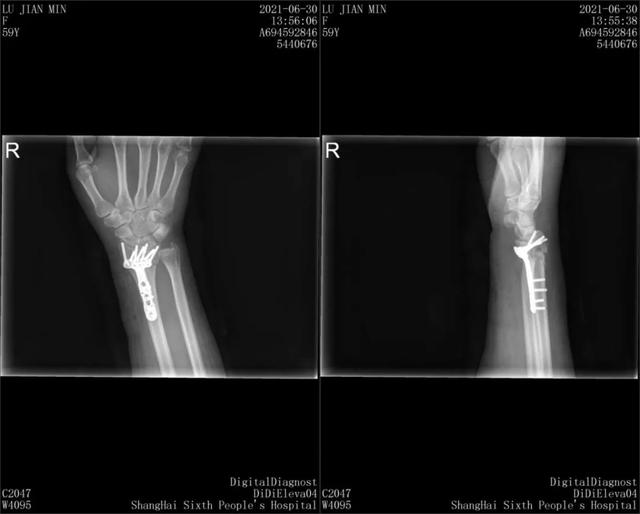

经医院诊断,陆女士伤势较为严重:

■右尺骨茎突骨折伴桡骨远端骨折;

■预计会造成十级伤残。

X光显示陆女士手部两根骨头骨折